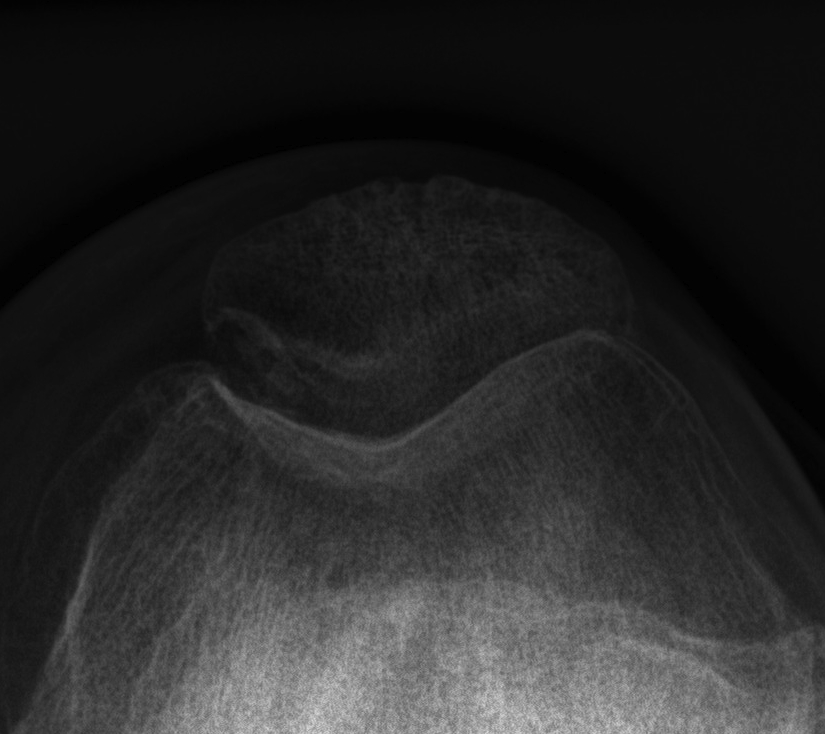

X-rays

AP / Lateral / Skyline

Patient 1